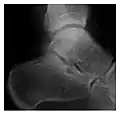

Figure 3: A 26-year-old man presenting with wrist pain after being assaulted. (a) Initial anteroposterior radiograph shows a subtle linear lucency within the scaphoid extending to the scaphocapitate articular surface that was overlooked (arrow). (b) Initial "scaphoid" view was negative. (c) Followup anteroposterior radiographs, 12 days later, shows obvious scaphoid fracture (arrows).[1]

High-energy trauma fractures

Occult osseous injuries may result from a direct blow to the bone by compressive forces of adjacent bones against one another or by traction forces during an avulsion injury. Lesions in the tibial plateau, hip, ankle, and wrist are often missed. In a tibial plateau fracture, any disruption of the posterior and anterior cortical rims of the plateau should be sought. Impaction of subchondral bone will appear as an increased sclerosis of the subchondral bone (Figure 1). In the hip, posterior acetabular fractures also present subtle radiographic findings. The acetabular lines should then be carefully examined keeping in mind that the posterior rim, which is harder to see on X-rays, is more frequently fractured than the anterior rim (Figure 2). In the wrist, detection of carpal bone fractures is often challenging, with up to 18% of scaphoid fractures radiographically occult. Carpal fractures, especially the scaphoid, are associated with the risk of avascular necrosis. In apparently normal wrist radiographs from symptomatic patients, if there is history of a fall on an outstretched hand with pain in the anatomic snuffbox, suggesting scaphoid injury, the initial examination with posteroanterior, lateral, and pronation oblique views must be complemented by other specific views such as supination oblique and the "scaphoid" view A careful examination of cortices for evidence of discontinuity or offset and cancellous bone for lucency is necessary (Figure 3).[1]